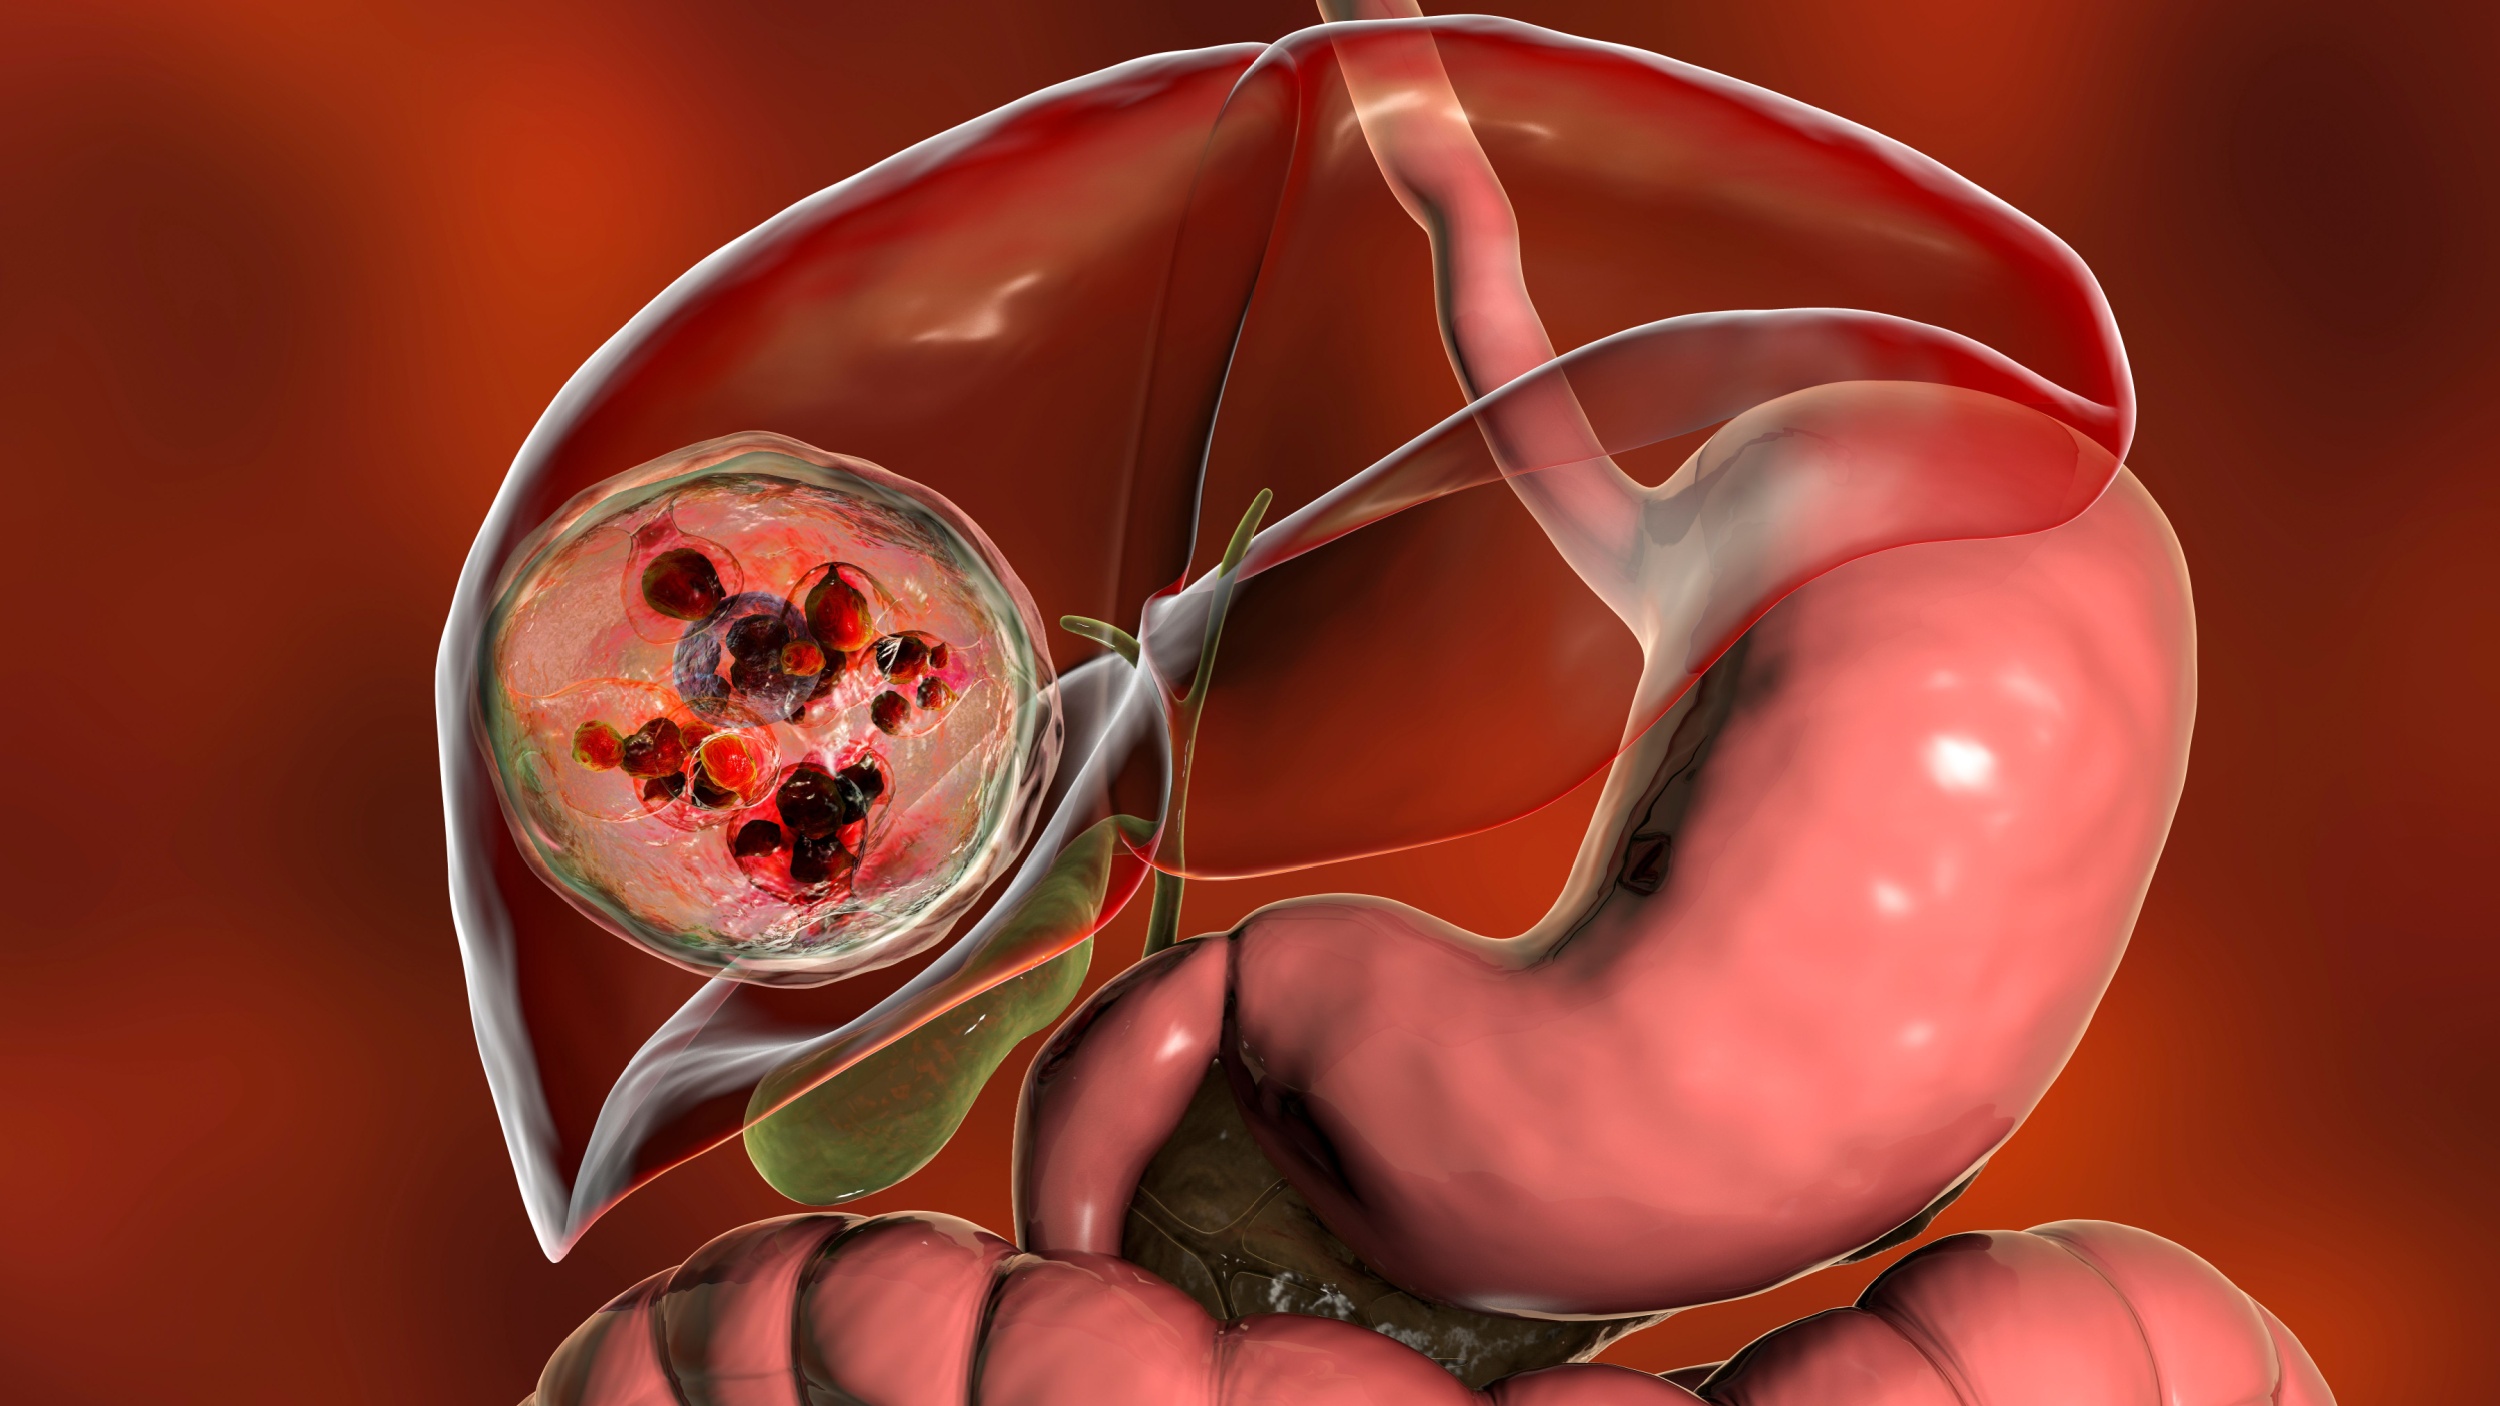

Эхинококк Печени Фото

Эхинококк Печени Фото 112 фотографий